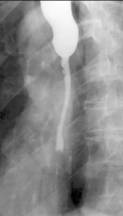

Dupa aproximativ 6 luni, evolutia leziunii este completa,

procesele de fibroza si scleroza determinānd stenoza. Dupa

acest interval de timp, prin examinarea cu bariu se pot face aprecieri asupra

existentei, localizarii si gradului procesului de stenoza

Imagistic se observa o īngustare a lumenului esofagian. Zona de stenoza cuprinde un segment lung, localizat de obicei sub strāmtoarea aortica. De cele mai multe ori este asociata cu stenoza gastrica antrala. Alteori se pot forma stenoze multiple, etajate.

Esofagul supraiacent este dilatat, īn pīlnie.